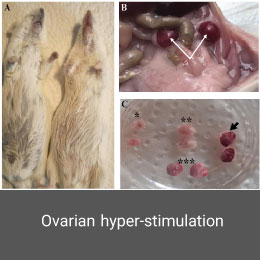

- Create and induce a variety of animal models